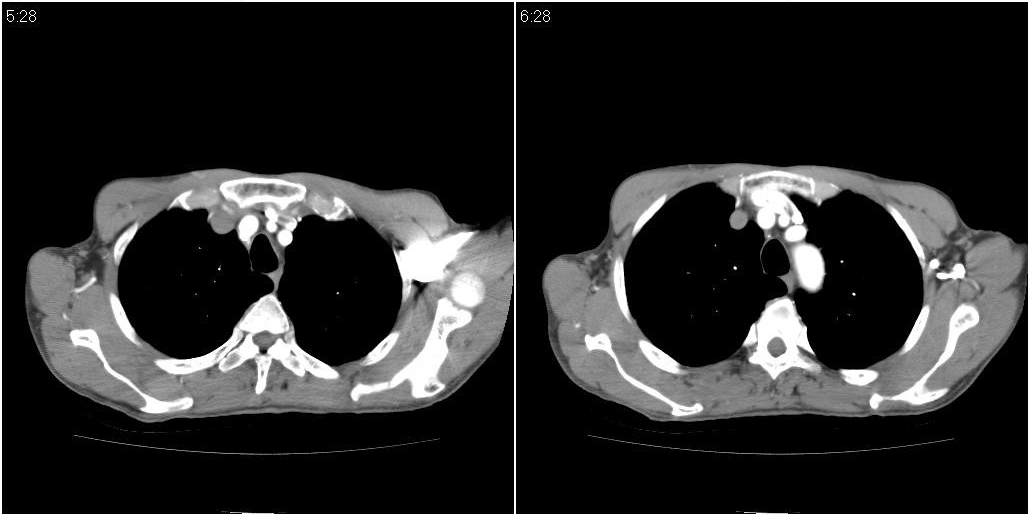

标题: CT25416:男性,70岁。胸片发现右下肺斑片状阴影 [打印本页]

标题: CT25416:男性,70岁。胸片发现右下肺斑片状阴影

以下是ct检查的情况:

考虑右肺下叶炎症可能性大?未除占位,建议增强。右下肺肺不张

右下胸壁皮下气肿。